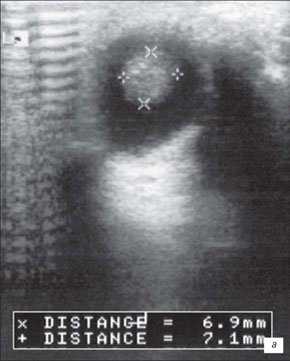

Является обязательным исследованием, в соответствии со стандартом обследования при таком заболевании. Одной из самых информативных методик признана УЗ-биолокация. Благодаря ей, выявляются плюс-ткани, и это позволяет отличить ретинобластому от отслойки сетчатки, эндофтальмита, фиброза стекловидного тела, ретролентальной фиброплазии.

Чтобы определить величину затухания УЗ в опухоли используют квантитативную эхографию. Для получения информации о динамике злокачественного процесса важное значение имеет УЗ-эхобиометрия. С ее помощью определяют степень проминенции (т. е. то, насколько оно выступающее) новообразования.